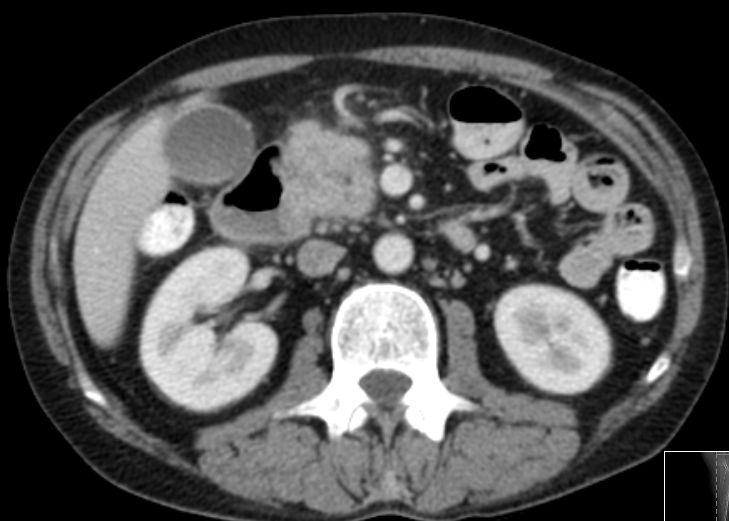

| Lokalrezidiv | 48-jähriger Mann mit Pankreaskopfkarzinom. Verschlussikterus, Bilirubin 99. ![]() |

CT: Einbruch ins Duodenum